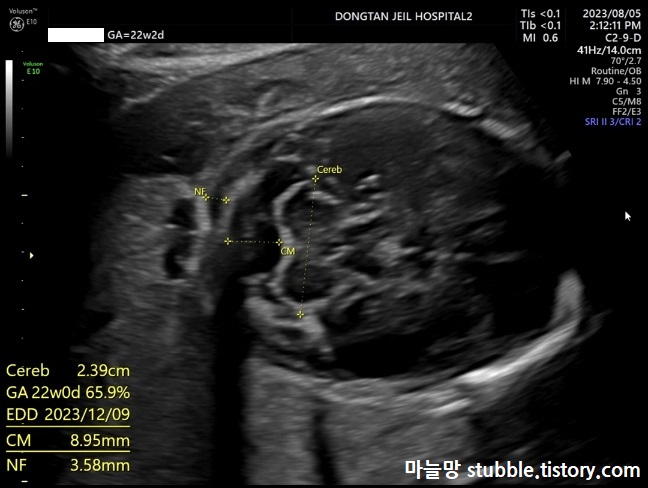

11. 소뇌크기 (Cereb) / 숨뇌크기 (CM) / 목투명대 두께 (NF)